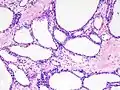

Pathologists classify serous cystic neoplasms into two broad groups. Those that are benign, that have not spread to other organs, are designated "serous cystadenoma".[5] Serous cystadenomas can be further sub-typed into microcystic, oligocystic (or macrocystic), solid, mixed serous-endocrine neoplasm, and VHL-associated serous cystic neoplasm. This latter classification scheme is useful because it highlights the range of appearances and the clinical associations of these neoplasms. Serous cystic neoplasms that have spread ("metastasized") to another organ are considered malignant and are designated "serous cystadenocarcinoma".

Pathology